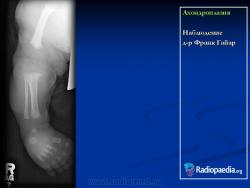

Наблюдение д-ра Франк Гайар

Характерными признаками гетерозиготной ахондроплазии являются укорочение конечностей, поясничный лордоз, короткие пальцы, макроцефалия с выступающим лбом и запавшей переносицей. Трубчатые кости, как правило, сохраняют правильную форму. Их деформация встречается не более чем в 25-30% наблюдений. Грудная клетка и живот не отстают от нормативных для срока значений.